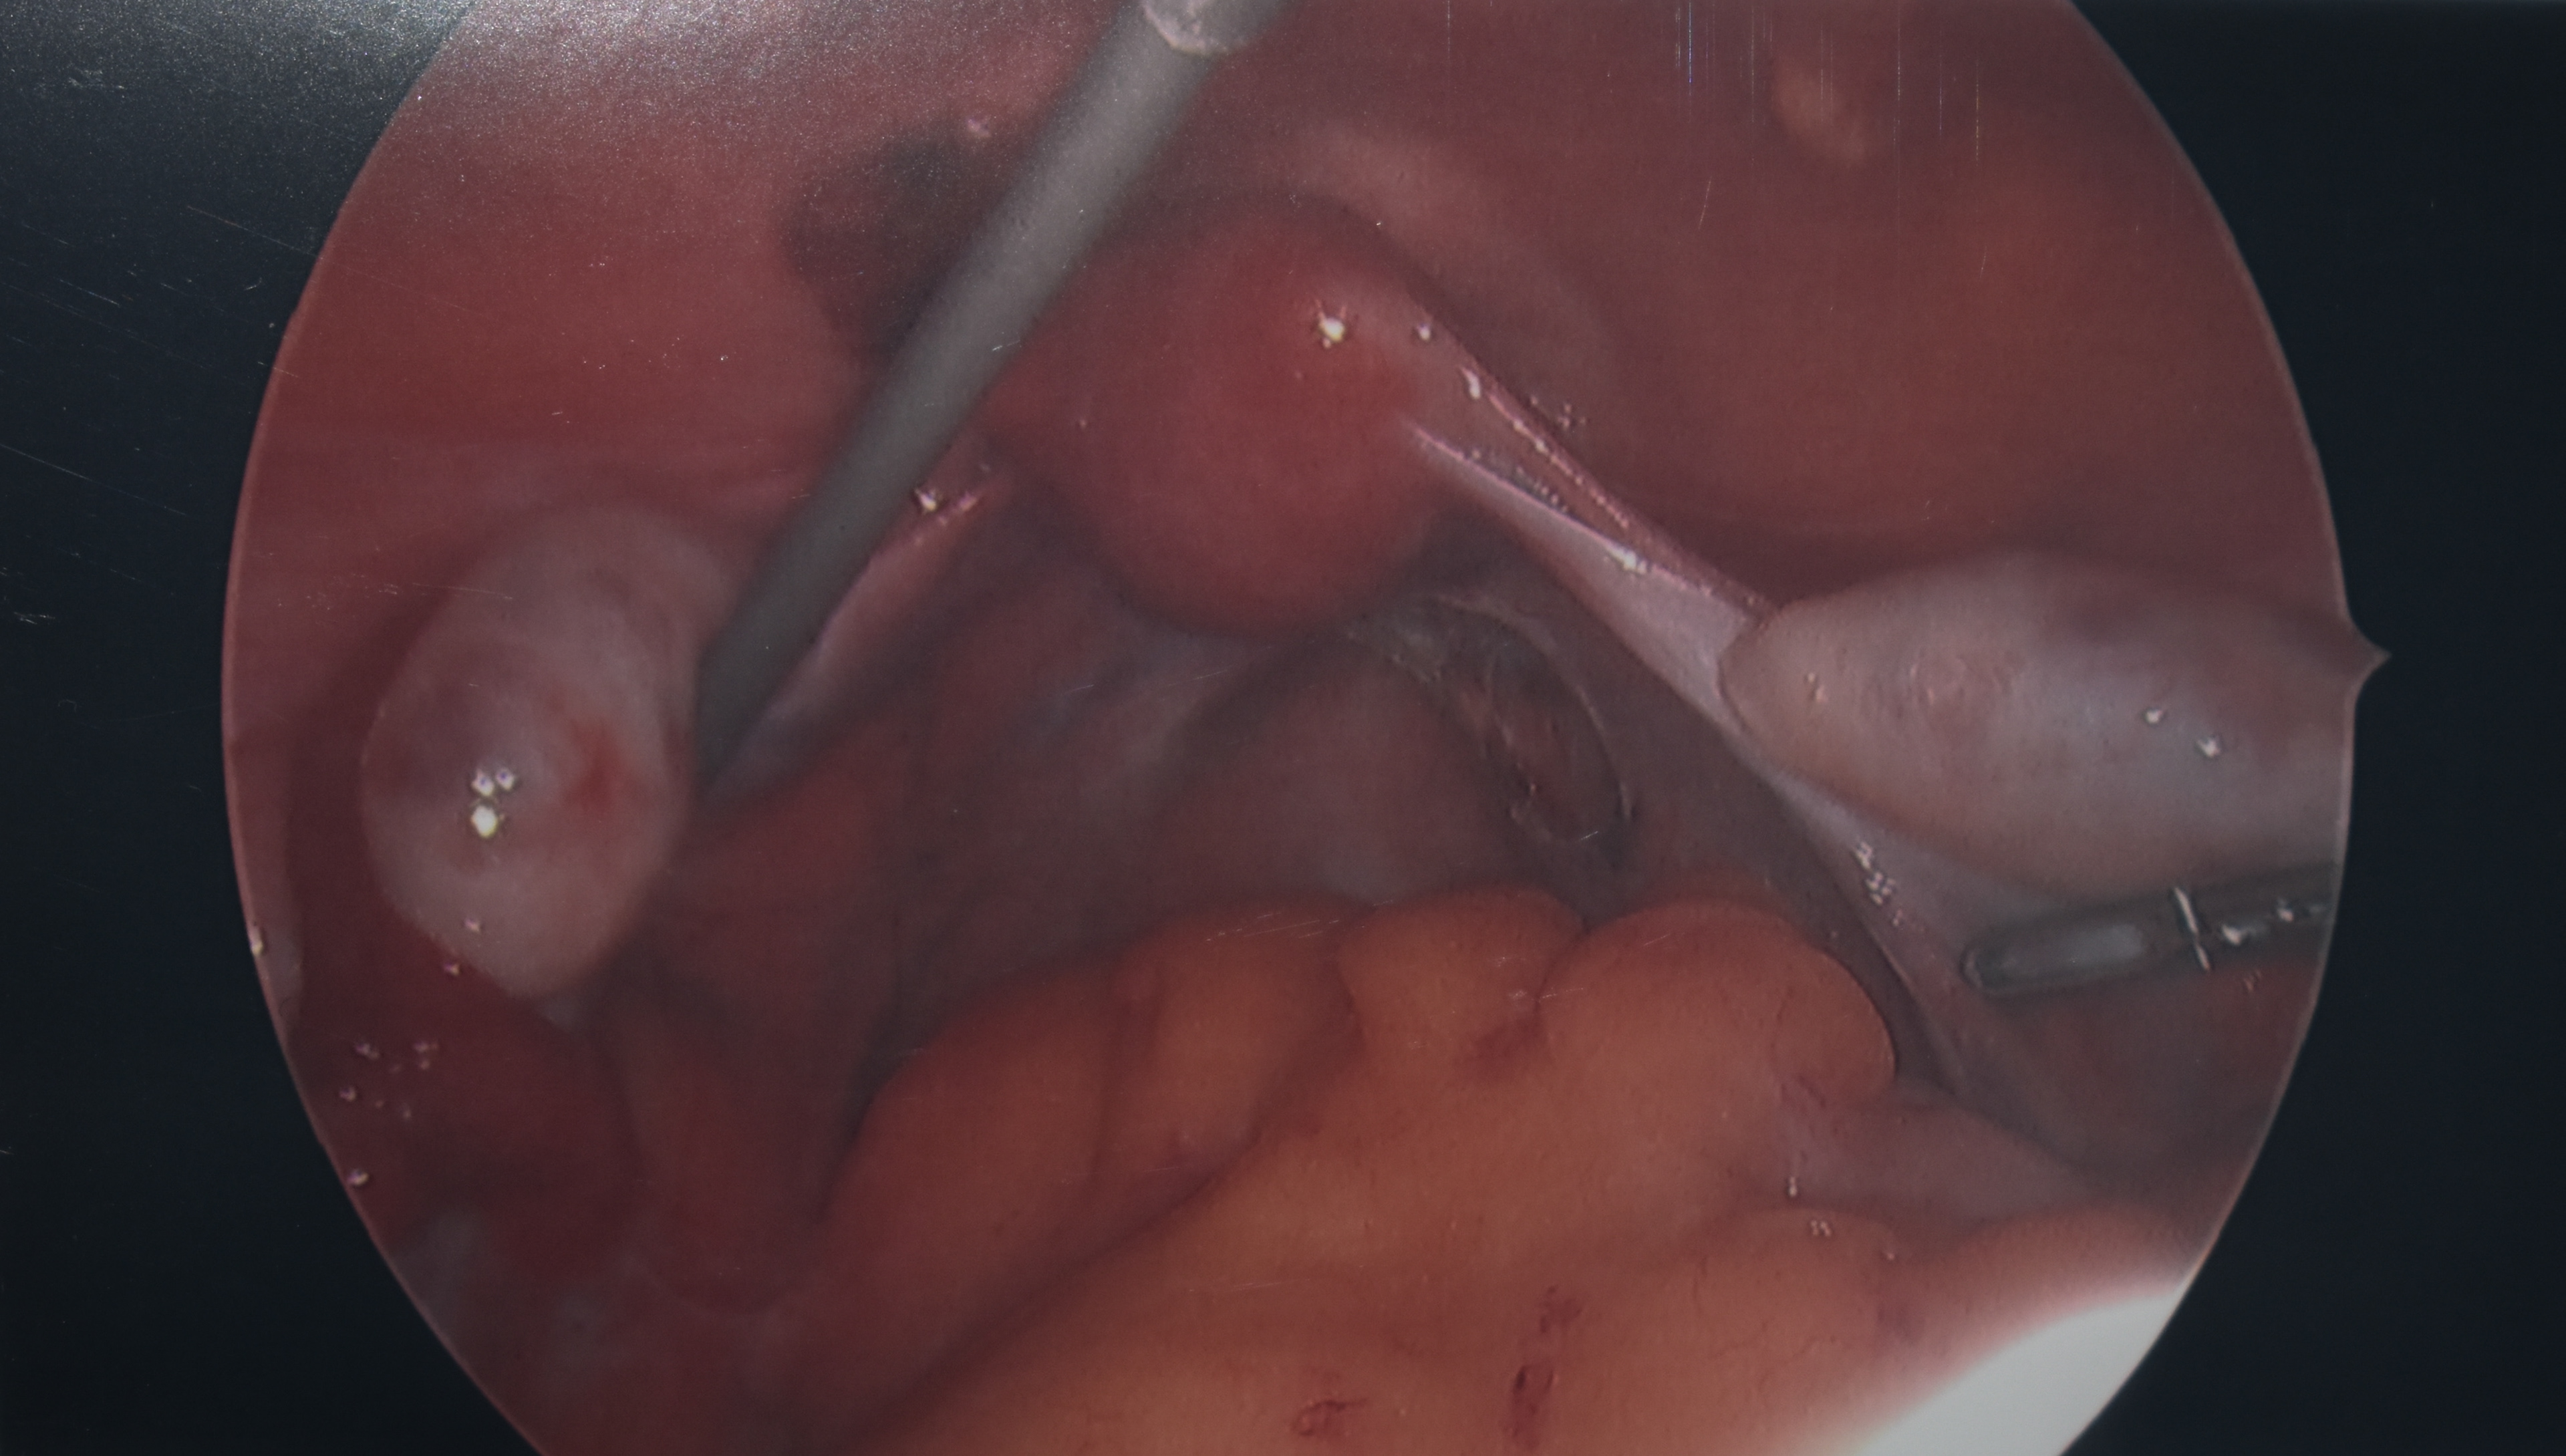

Many people end up  having a hysteroscopy and laparoscopy to diagnose endometriosis or look for signs of adenomyosis. Photo: Ella Kinrade